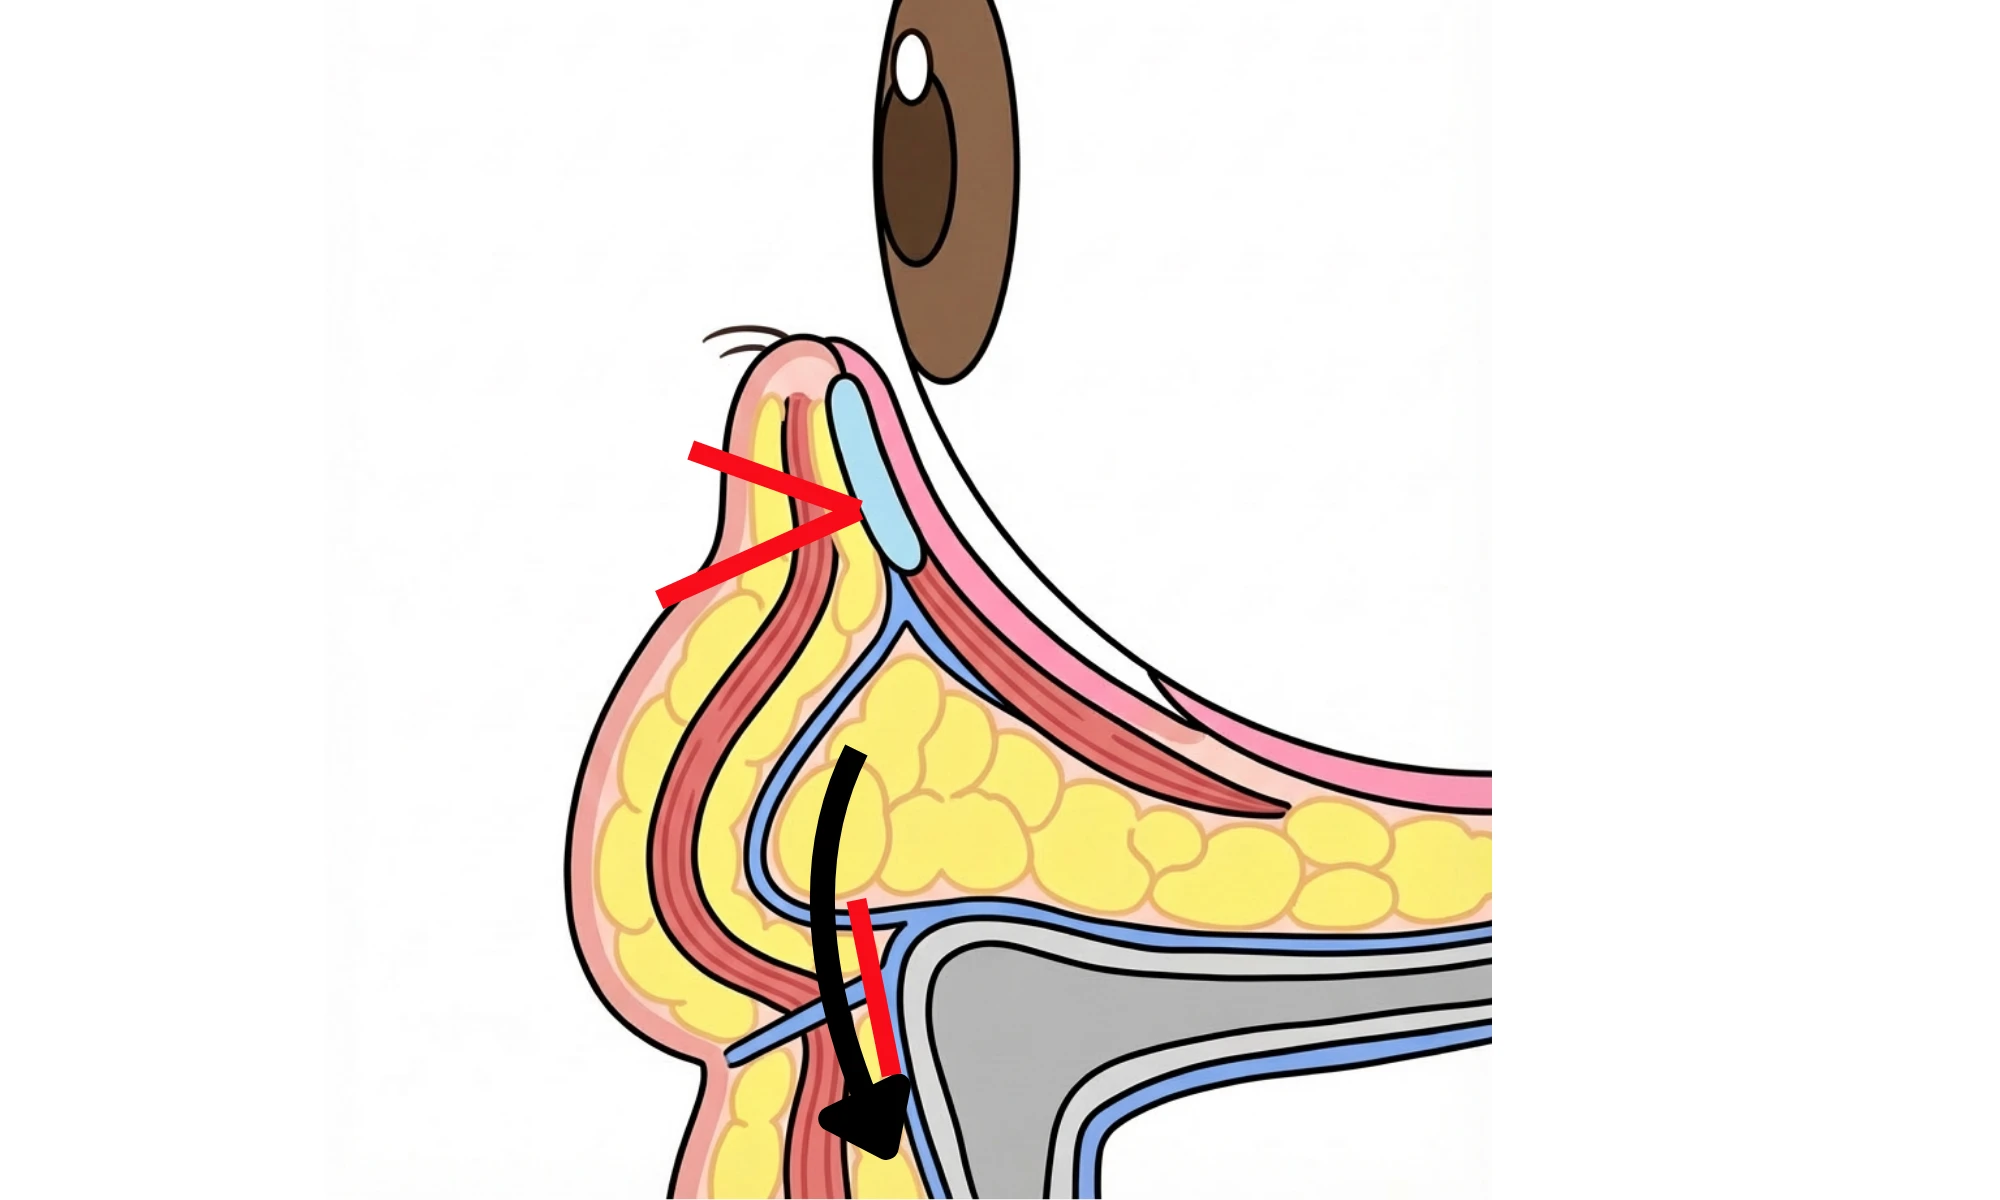

表ハムラ法とは、まつ毛の生え際部分から下まぶたの皮膚を切開し、

骨と皮膚を繋ぐ強い靭帯の解除し、眼窩脂肪の再配置、余剰皮膚切除を行う手術です。

当院では、無理な皮膚切除による不自然な変形を防ぐため、皮下組織(眼輪筋)の固定力を高める手技を重視しています。

土台となる組織を適切に吊り上げ、補強した上で皮膚を整えることで、自然な仕上がりと長期的な維持を追求します。

裏ハムラ法と同様に、表ハムラ法でも、くぼみの原因となる靭帯の癒着を丁寧に解除します。

そのうえで、眼窩脂肪を前方へ再配置することで、再癒着を防ぎながら、

眼窩縁〜ティアトラフ(目頭側)の食い込みや段差をなだらかに整えます。

皮膚を切り取る手術で最も避けるべきは、下まぶたが外側にめくれる外反です。

当院では、土台となる眼輪筋を骨膜へ確実に吊り上げて固定することで支持力を高め、その上で余剰皮膚を整理します。